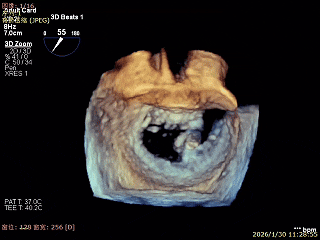

3D Enface 2区及3区前叶脱向左房

3D Enface 可见反流由2区3区从前后冲出

3D Enface下组织桥稳定残余外侧前叶脱垂

3D Enface上彩可见夹子内侧无反流,残余外侧反流

3D Enface下组织桥稳定无反流

夹子释放后,反流基本消失